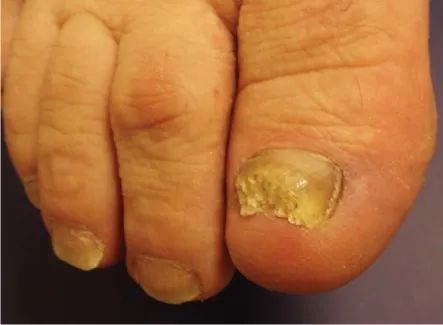

指甲增厚

常由甲真菌病引起,除了增厚外,指甲还可有变色、变形等特征。

甲真菌病。